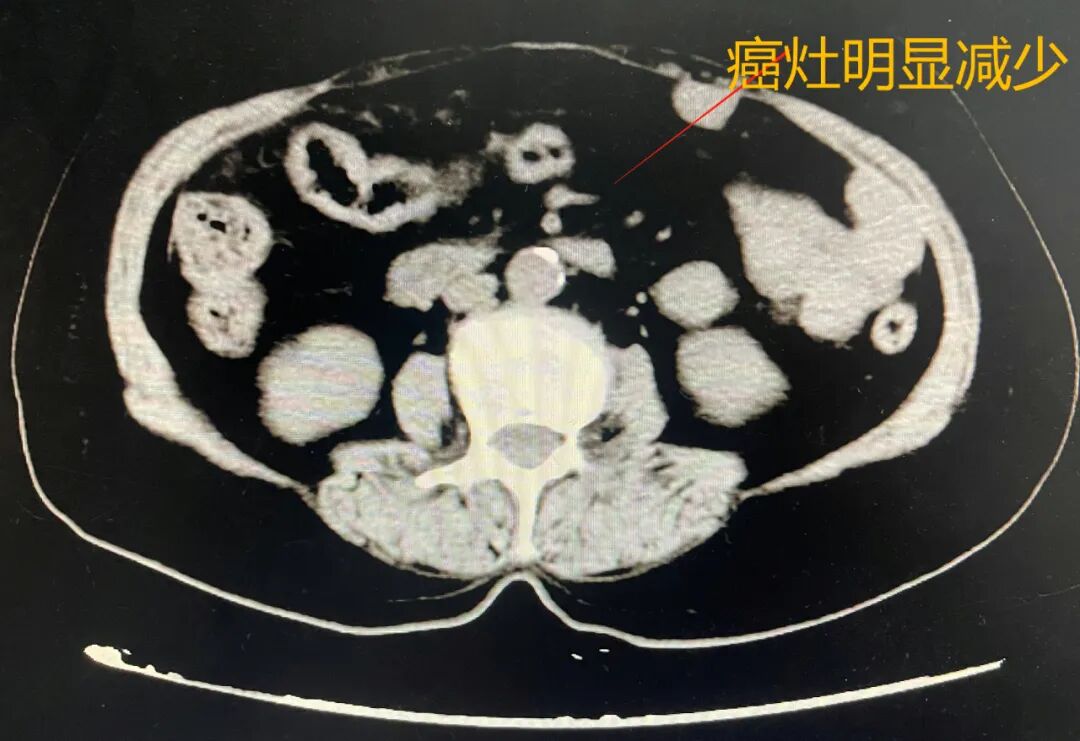

为了解决治疗中可能碰到的各种难题,在妇科主任张圆圆的主持下,组织了肾病科、麻醉与围术期医学科、手术部、医学影像科等多学科会诊。在肾病科主任刘建林的指导下,给予患者保肾药物治疗,同时根据患者卵巢肿瘤病理类型、血肌酐、尿素氮的情况,选择化疗药物及药物的用量,在化疗过程中妇科多次联系医学影像科主任周青,综合对比患者化疗前及化疗后的病灶变化,确定最佳手术时间。

经过3个疗程的化疗后,影像学结果提示卵巢肿瘤、大网膜及肠系膜多发转移病灶较前明显缩小。遂决定进行手术治疗,术前请麻醉与围术期医学科主任医师洪道先会诊,综合评估患者病情,认真研究术中、术后可能出现的并发症及预防应对措施。